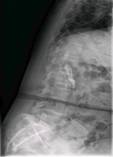

术后患者立即感到腰腿部不适明显缓解,术后24小时左右已在保护下站起,室内锻炼行走。术前症状几乎完全消失。术后复查X线片显示:腰5-骶1椎间隙高度较术前明显恢复,腰5椎体滑脱完全纠正,融合器位置理想。

术后复查腰椎正侧位